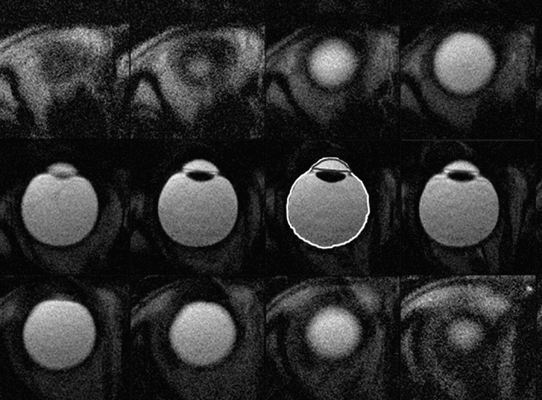

Что покажут снимки МРТ головы с контрастом при лимфоме глазницы

- Изоинтенсивное объемное образование на Т1 - и Т2-взвешенном изображении

- Выраженное усиление сигнала после введения гадолиния

а, b Двусторонние внутриглазничные лимфомы. На Т1 -взвешенном изображении очаги выглядят как гипоинтенсивные объемные образования (а) с выраженным усилением после введения гадолиния (b).